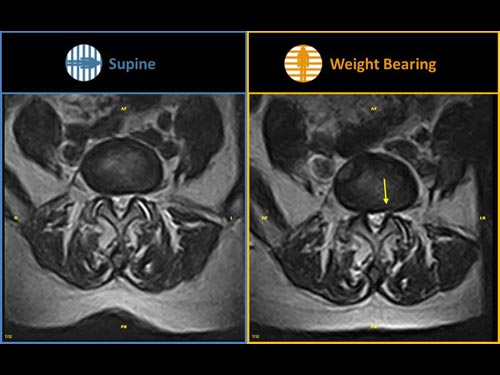

Nová končetinová magnetická rezonance G-scan Brio od společnosti Esaote je tomografický systém MRI, který umožňuje studium všech kloubů i páteře, ať už v klinostatické (vleže) nebo ortostatické (vážící) poloze, protože magnet i pacient se mohou otáčet od 0 do 90 stupňů. Díky inovativnímu designu G-scan mohou být pacienti Brio skenováni v poloze nesoucí váhu, aby se usnadnila diagnostika MSK u těch patologií, které se mohou měnit v důsledku držení těla a polohy, jako jsou bolesti dolní části zad.

• Váhové ložisko: poloha pacienta se stává nedílnou součástí výsledku vyšetření

• Další diagnostické schopnosti: jelikož gravitační síla generuje bio-mechanické změny v anatomii, MR zobrazení v přirozené poloze ve stoje vám umožňuje dosáhnout důležitých dalších informací ve srovnání s tradičními MRI

G-scan Brio je speciálně navržen pro všechny aplikace pohybového aparátu. Otevřený a naklápěcí design je nový a inovativní způsob provádění MRI, při kterém se poloha pacienta stává nedílnou součástí výsledku vyšetření. G-scan Brio poskytuje pacientovi vysoký komfort s funkcí nejnovějšího zobrazovacího výkonu a sekvencí společnosti Esaote.